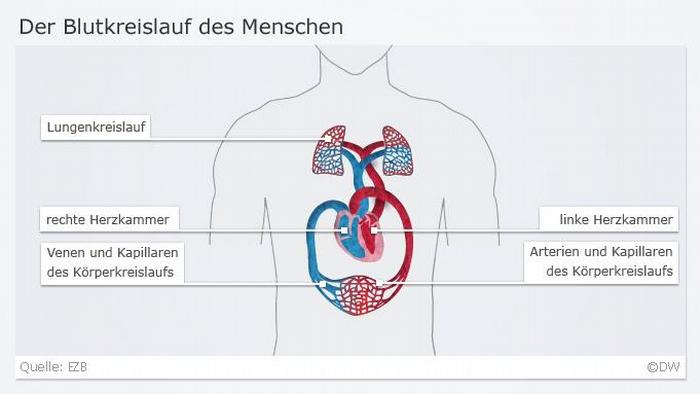

يتكون القلب من قسمين وكل قسم من القلب يحتوي على أذين وبطين. وجسم الإنسان يتكون من جهازين لدوران الدم وليس من جهاز واحد. لأن القسم الأيمن من القلب يضخ الدم إلى الرئتين لتزويد الدم بالأوكسجين، وفي الوقت نفسه يضخ القسم الأيسر من القلب الكمية نفسها من الدم إلى أنحاء الجسم. وترتبط أجزاء القلب مع بعضها بصمامات تسمح بمرور الدم باتجاه واحد وتمنع رجوعه في الاتجاه المعاكس.